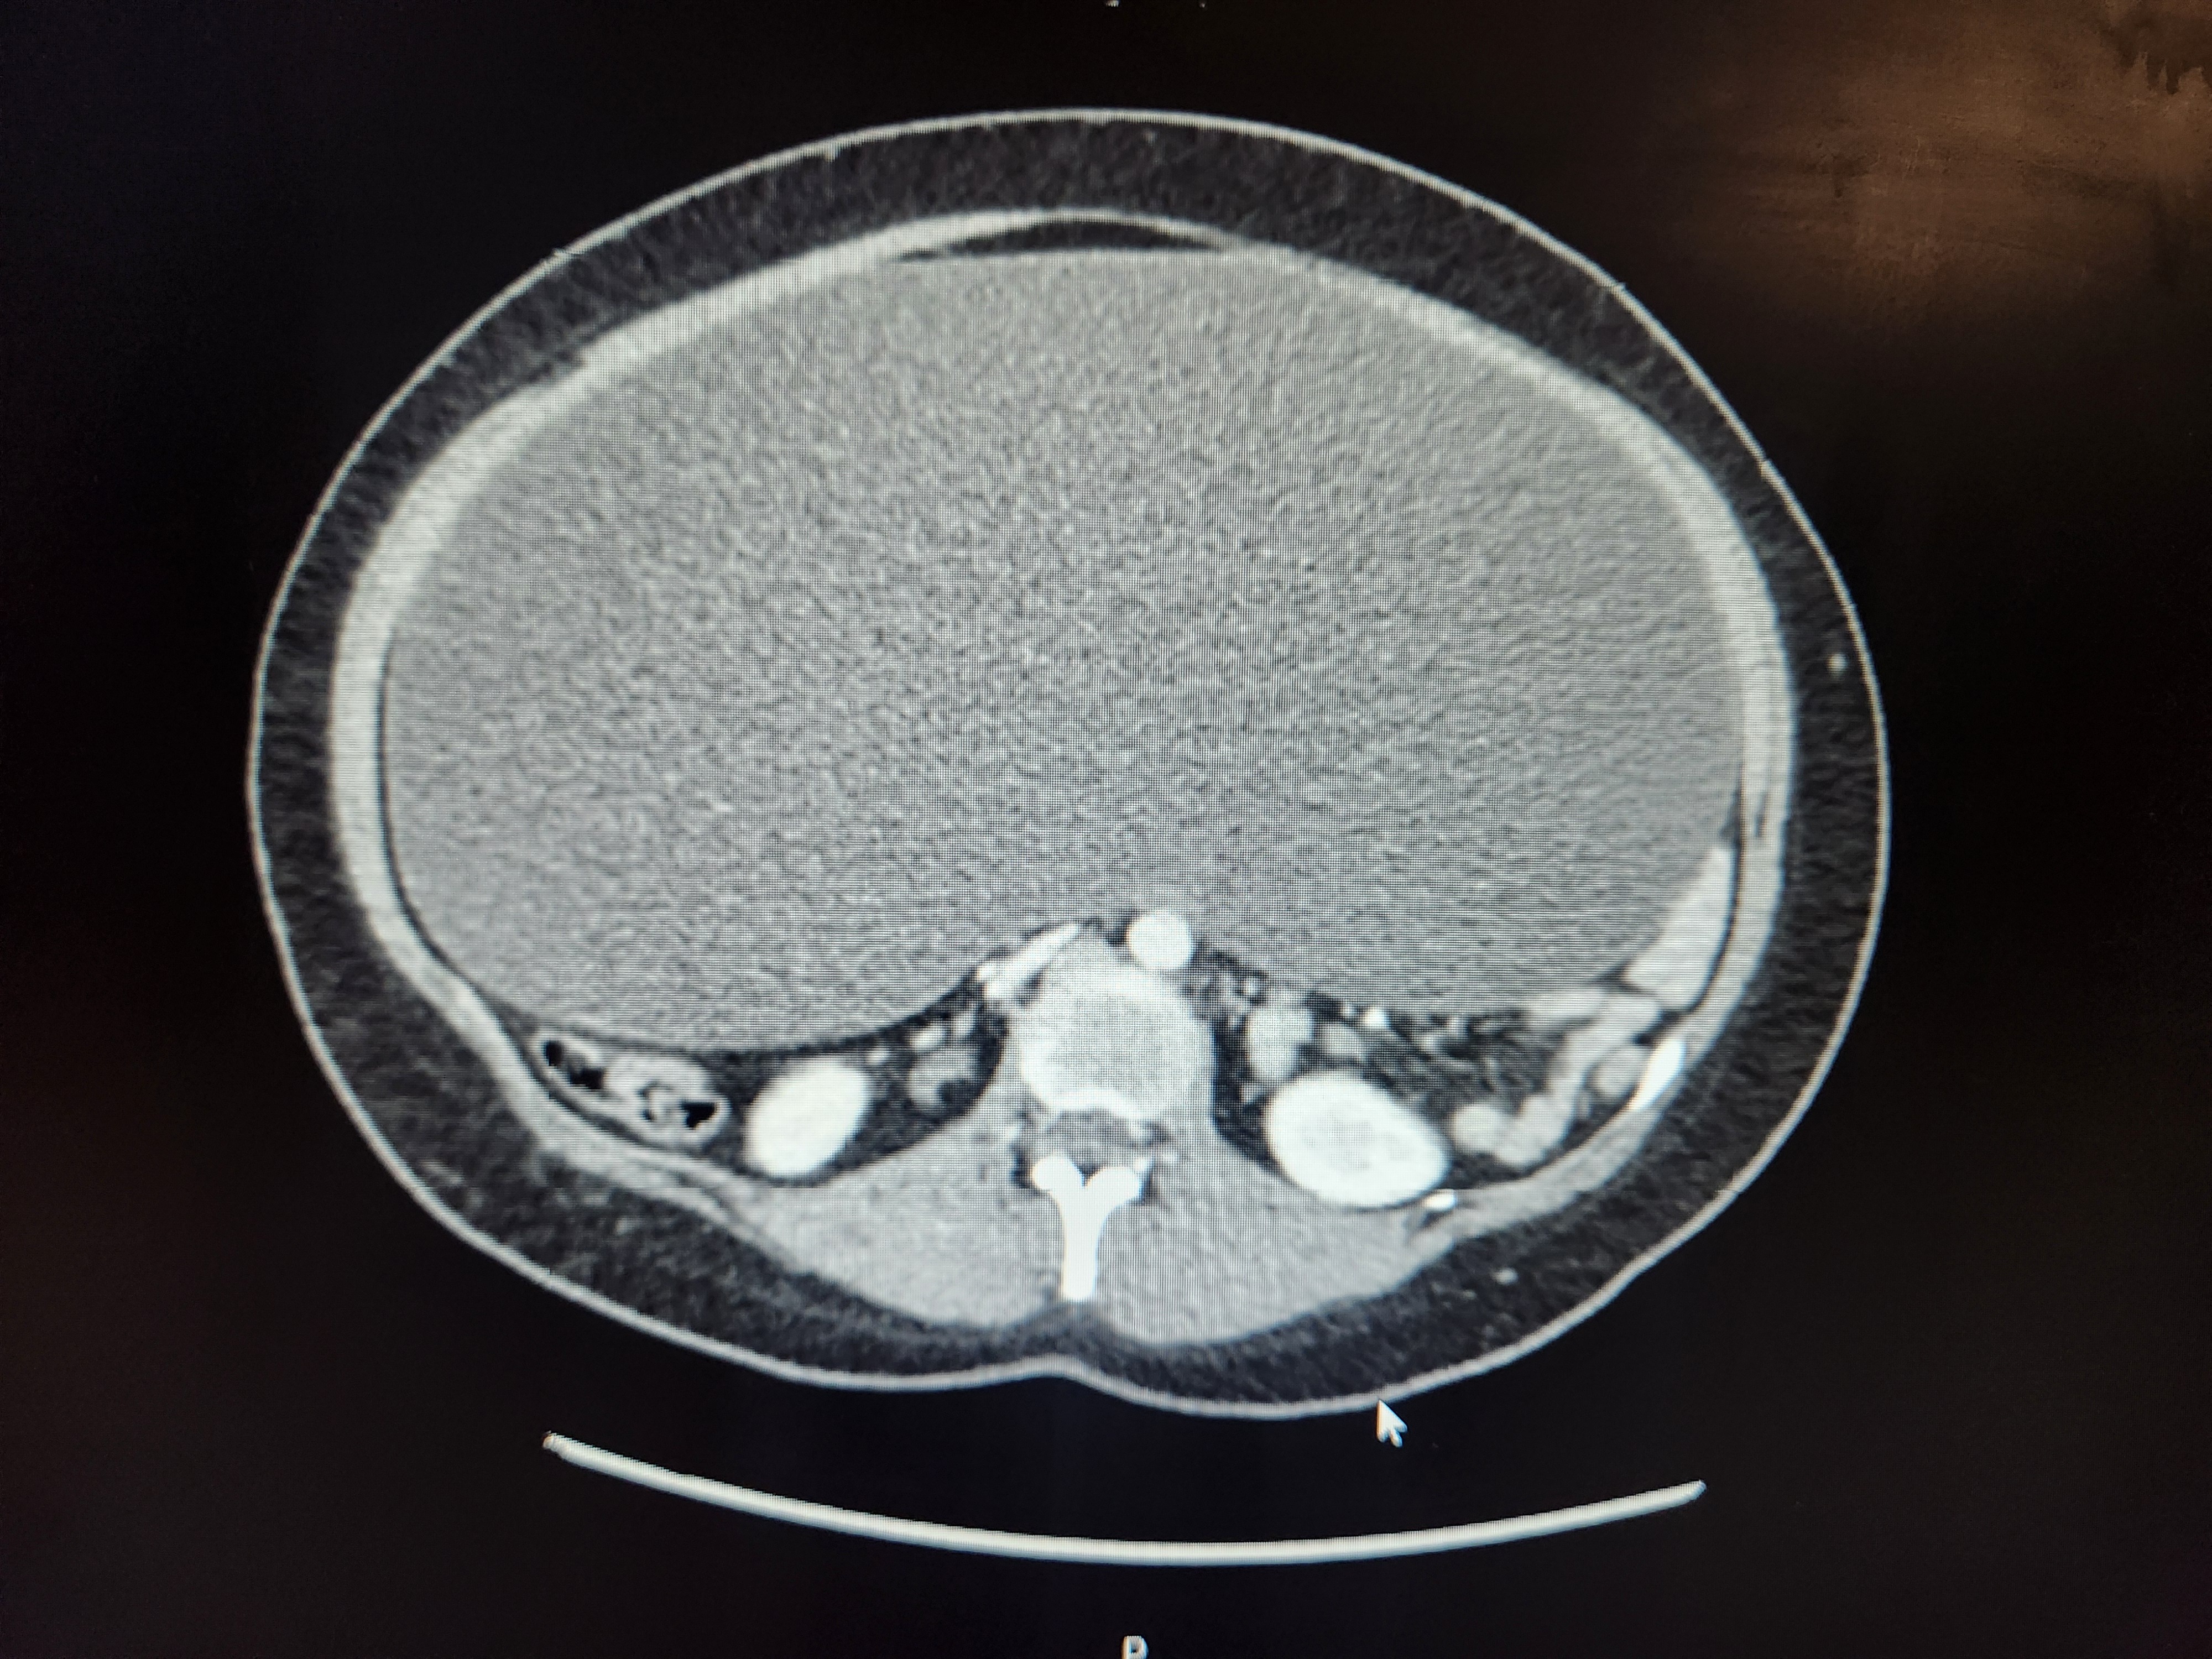

MANY hours in the local ER, labs, more labs, 3x ultrasounds, CT, pelvic & abdominal MRIs, consults with GYN, GYN/OC, hospitalists, GI, & urology... revealed Bella has a MASSIVE serous fluid-filled cyst (tumor) filling her ENTIRE ABDOMINAL CAVITY. It is pushing on the bottom of her heart & stretches down to her private area where it is completely compressing her Right ureter, causing R kidney backflow. Where her lower R ovary is she has a solid distended mass, most likely the malignant root of the larger cyst. Her stomach, liver, lungs & spleen are being pushed up & back towards her heart. Her intestines are severely compressed into her spine.

The Beast has made itself known. Very quickly it became obvious Bella's vomiting was hard to control (everything is being forced up) & her pain has increased dramatically as the mass has reached... critical mass on her organs. She can no longer eat or use the restroom, she can't lay down or the pressure-pain is excrutiating, & she struggles to breathe.